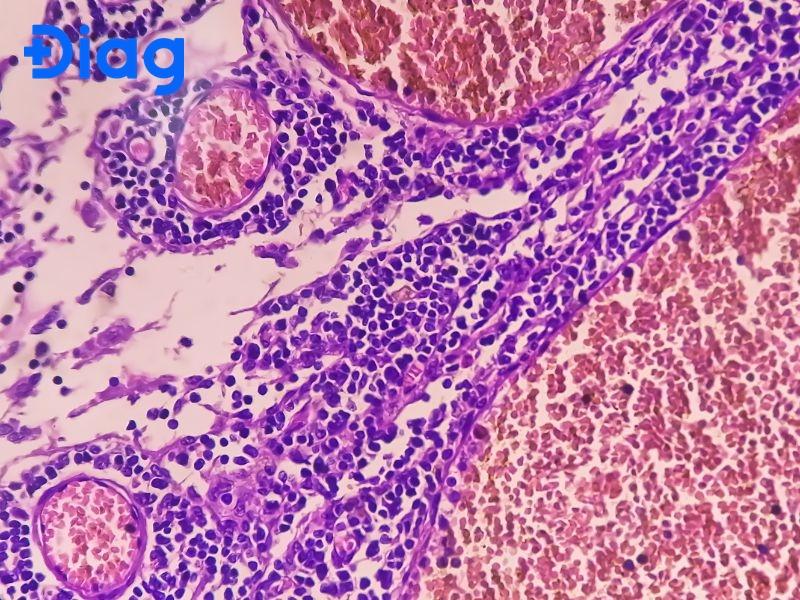

- Lấy mẫu sinh thiết mô và xét nghiệm mô học: Lấy mẫu mô sinh thiết là bước quan trọng nhất để chẩn đoán ung thư biểu mô tuyến kém biệt hóa. Tế bào kém biệt hóa thường có hình thái rất bất thường, nhân tế bào lớn, mất cấu trúc tuyến điển hình, cho thấy sự phân hóa kém.

- Các kỹ thuật chuyên sâu khác: Nhuộm miễn dịch hóa học hoặc phân tích tế bào để xác định đặc điểm khối u chi tiết. Các phương pháp này giúp bác sĩ đánh giá chính xác loại ung thư và mức độ biệt hóa để đưa ra phác đồ điều trị hiệu quả.